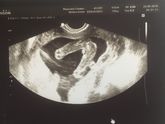

Вот,девочки. То о чем писаоа ранее. Уже месяца полтора,в день раз по 5 твердеет сбоку и вылезает полукруг. Так все время только справа!!поэтому и задумалась не косое ли предлежаник у ребенка. С левой силроны никогда такого нет и всегда мягко. А справа … Читать далее